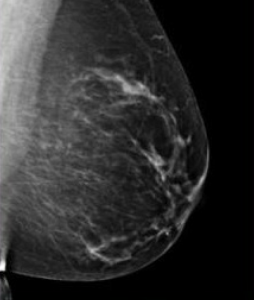

Women who have dense breasts have a slightly higher risk of breast cancer than women with less dense breasts. Dense breast tissue makes it more difficult for radiologists to detect cancer, because both dense breast tissue and masses or tumors look white in mammograms.

Breast density can only be seen on mammograms, and cannot be determined by how your breasts feel. The radiologist will determine your breast density while reading your mammogram. Results will be included on the mammography report sent to you and your physician. A 4-level scale (pictured to the right) is used to categorize density.